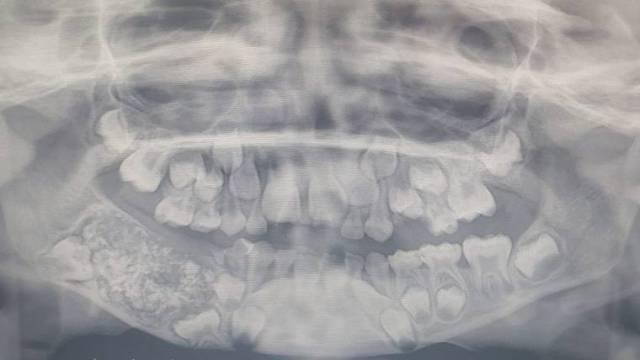

Cuando los médicos escanearon y le tomaron radiografías de la boca, encontraron un saco incrustado en su mandíbula inferior lleno de “dientes anormales”, dijo el Dr. Prathiba Ramani, jefe de Patología Oral y Maxilofacial del Saveetha Dental College and Hospital.

Si bien la cirugía para extraer los dientes se realizó el mes pasado, los médicos necesitaron tiempo para examinar individualmente cada diente antes de poder confirmar sus hallazgos. El equipo de Ramani tardó de cuatro a cinco horas en vaciar el saco para confirmar su contenido y descubrió los cientos de dientes.

“Había un total de 526 dientes que iban desde 0.1 milímetros a 15 milímetros. Incluso la pieza más pequeña tenía una corona, raíz y capa de esmalte que indicaban que era un diente”, dijo.